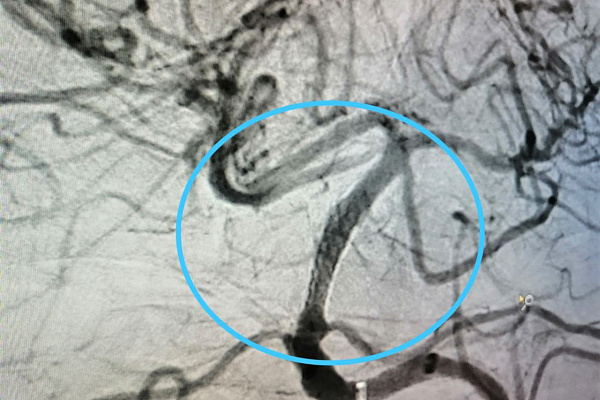

Поэтому следующим этапом оперативного лечения стала ангиопластика. Для неё используется баллонный катетер. Он вводится в сосуд и расширяется под давлением, устраняя стеноз. Как правило, такой «продувки» достаточно для восстановления сосуда в диаметре. Но в данном случае это помогло ненадолго – стенки артерии снова спадались, возвращаясь в прежнее положение. Тогда Максим Бессмертных принял решение об интракраниальном стентировании. Эта операция – из разряда крайних мер. Стентирования внутричерепных артерий при их сужении стараются избегать до последнего из-за высоких рисков.

-В отличие от сосудов сердца, сосуды головы менее прочные, их легче повредить при установке стента. Поэтому вмешательство является опасным и очень редким. Например, в 2021 году, по данным главного рентгенохирурга страны Баграта Алекяна, в России выполнено всего 55 таких операций, а количество стентирований коронарных артерий превысило 328 тысяч. В Сургутской травмбольнице за прошлый год проведено всего два интракраниальных стентирования. И в обоих случаях это был единственный шанс спасти человеку жизнь и дееспособность, – отмечает Максим Бессмертных.

Сохранить эффект от успешно выполненной ювелирной операции (фото №3) предстояло анестезиологам-реаниматологам. С учётом индивидуальных особенностей пациента они сумели подобрать антиагрегантную и анитикоагулоянтную терапию, чтобы избежать дальнейшего тромбоза стента. Это естественная реакция организма на инородное тело в любом сосуде, которая блокируется соответствующими препаратами.